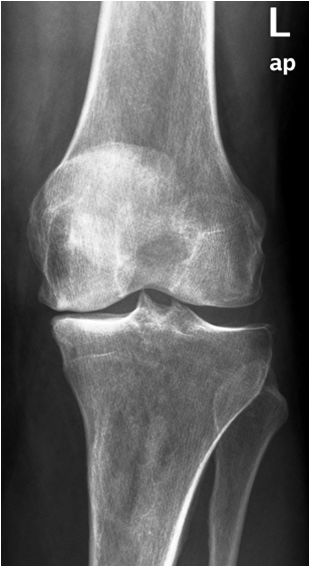

Primary osteoarthritis involves weight bearing joints such as the knee, where changes are seen especially in the medial compartment and the patellofemoral compartment. In the hip changes are seen superolaterally. The tibiotalar joint is rarely significantly involved, except for changes along the anterior margin of the distal articular surface of the tibia. These are most likely posttraumatic in origin.

Fig. 13. A) Knee joint with degenerative changes. Note the sclerotic medial tibial plateau and joint space narrowing. A small osteophyte is seen on the medial femoral condyle. B.) Pelvis with marked degeneration of both hip joints. The right femoral head shows lateral osteophyte formation and is deformed. The joint space is narrow with increased subchondral sclerosis of the acetabular roof. The left hip has a marked joint space narrowing and lateral osteophyte formation. The femoral head shows increased density due to sclerotic areas and irregularity.